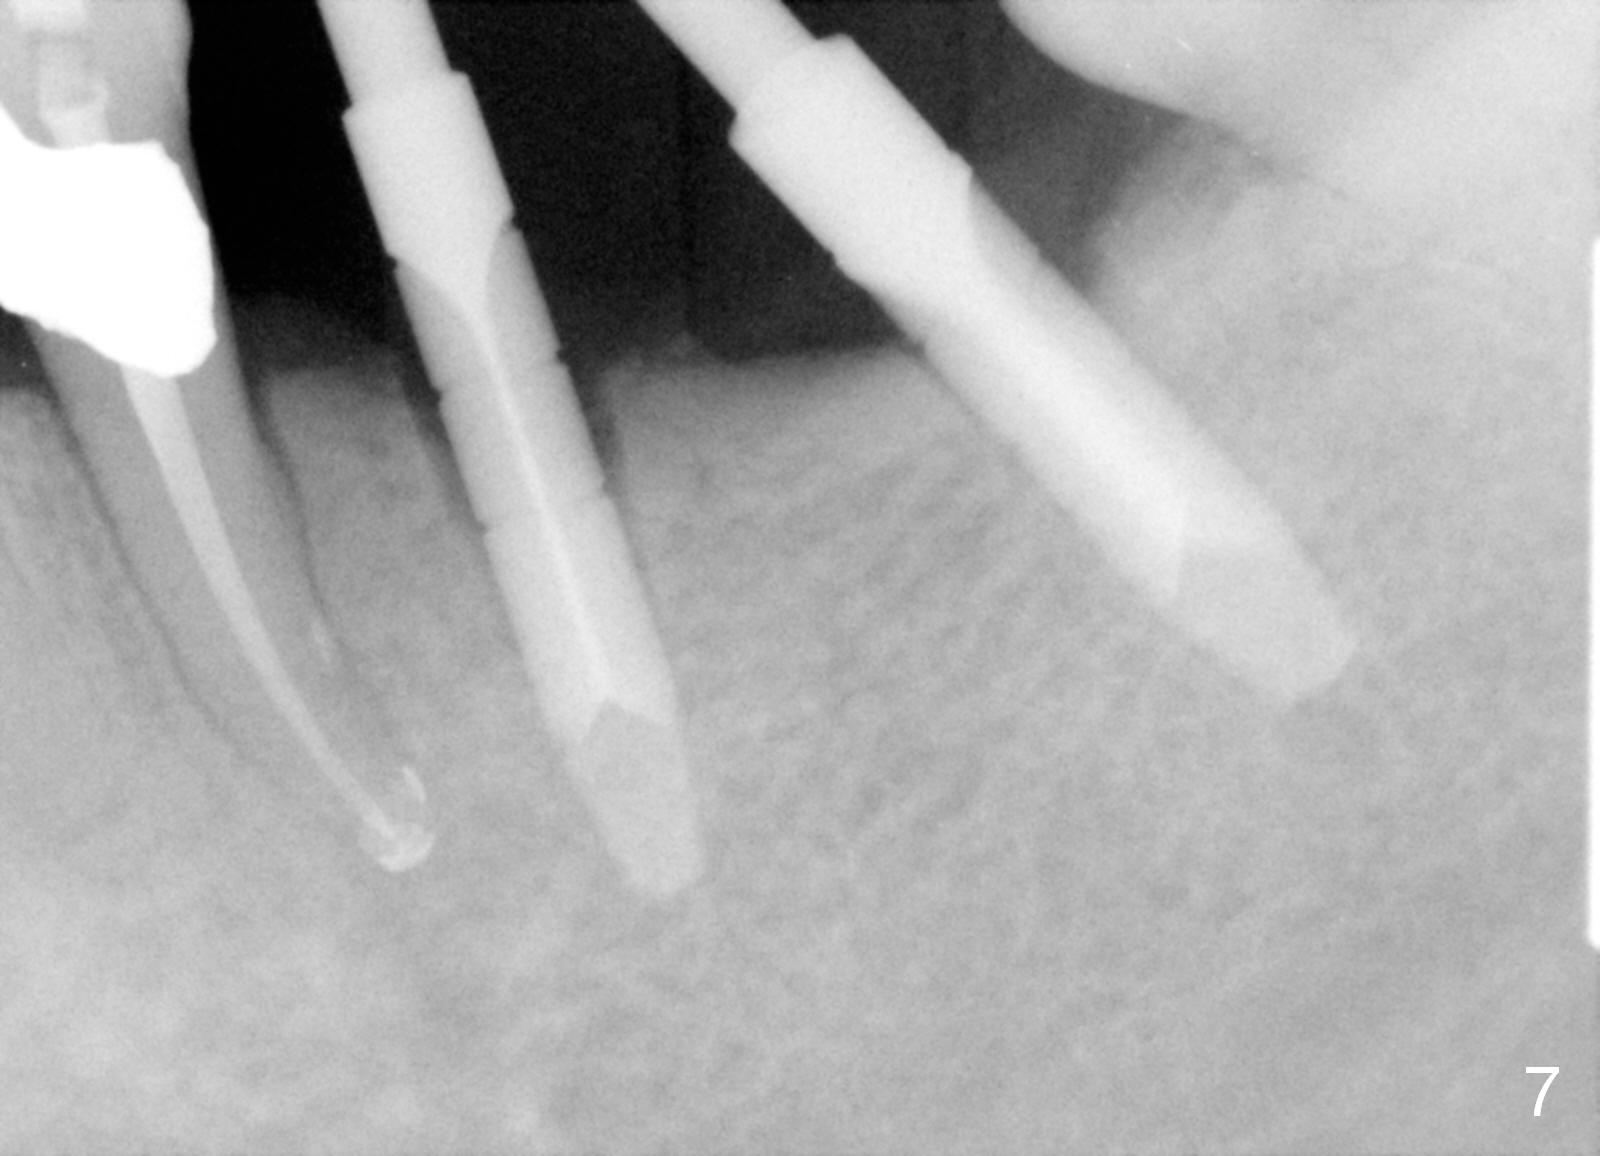

One year 2 months post root canal therapy at #20 (Fig.4), osteotomies are initiated at #18 and 19. The trajectory at #19 is subsequently corrected (Fig.5); that of #18 should be also corrected (arrow). The fact of the narrow ridge (Fig.6) is also ignored intraop. Without further adjustment, the osteotomies are enlarged (Fig.7) and the implants are placed (Fig.8: 4.5x14, 5x14 mm). As expected, the buccal coronal implant surface is exposed. The buccal plate is decorticated with placement of autogenous bone graft. Periodontal dressing is applied. Postop, the wound is infected with wound gapping. With irrigation, the wound finally heals.